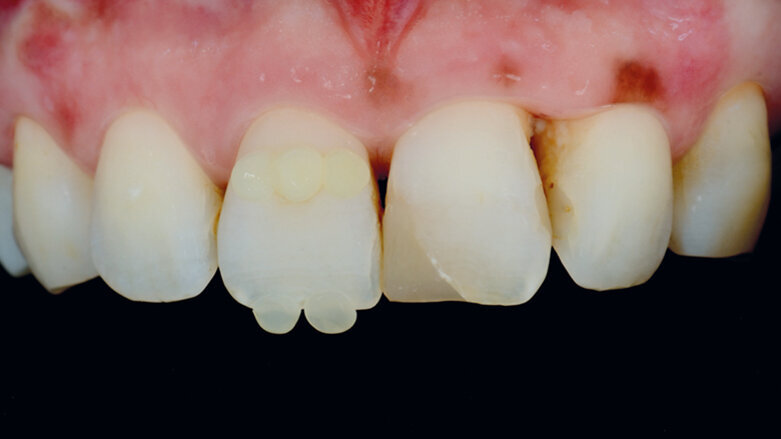

Výběr odstínu pomocí tzv. kompozitní „knoflíkové“ techniky (Composite Button Technique), s (4) a bez (5) polarizačních filtrů.